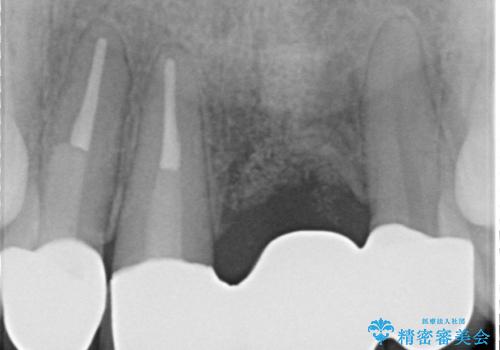

左側の前歯には他院で埋入されたポジションの悪いインプラント補綴により歯冠長の長いクラウンが装着されており、感染による排膿も認められこのまま審美性を改善するのは難しい状態です。

感染したインプラントからは排膿が間欠的に認められ、掻爬・除去が検討されうるような状況でした。

より審美的な改善を強く求められたため、インプラントを除去し可及的に欠損部顎堤を増大したのちブリッジによる審美改善を行いました。